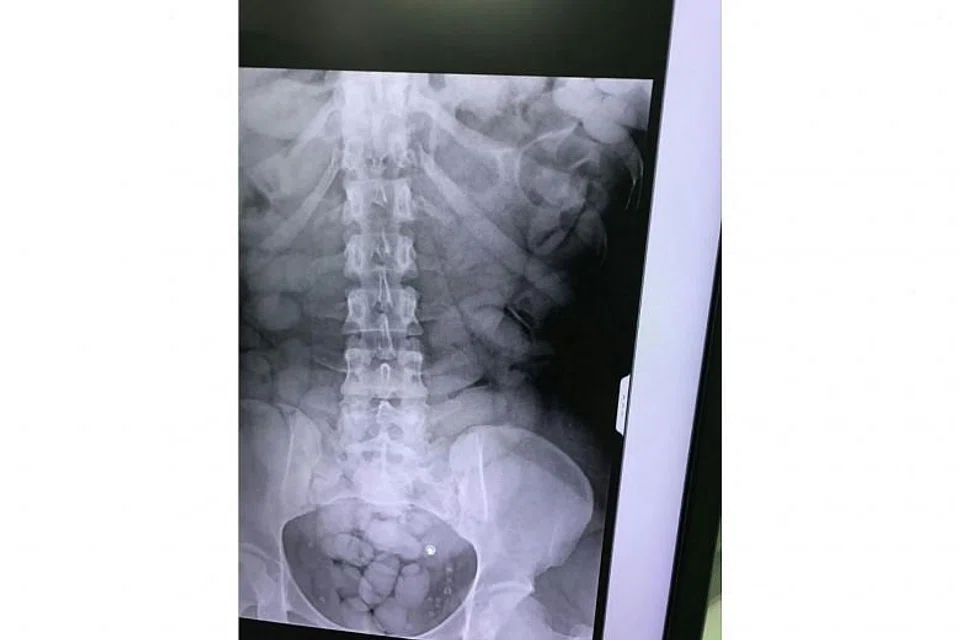

[BANGKOK] A 27-year-old woman from the Ivory Coast has been arrested on the Thai island of Phuket after an airport X-ray found more than 1kg of cocaine in her stomach wrapped in scores of small packets.

An X-ray revealed more than 60 small packages in her stomach, filled with 1.2kg of cocaine, according to Sirinya Sitdhichai, secretary-general of Thailand's Office of Narcotics Control Board.